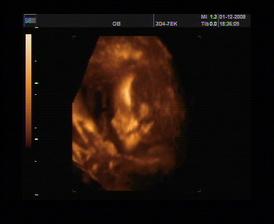

8.10.2008 ultrazvuk ve 20tt. Všechno probíhá normálně, prcek roste tak jak by měl. Měříme cca 20cm, váha 450 g. Hlavička odpovídá na 19+4, takže datum porodu nám potvrdili na 28. února. Chtěli jsme vědět pohlaví, ale bobek na nás vystrčil prdýlku a máme si prý trhnout ☹